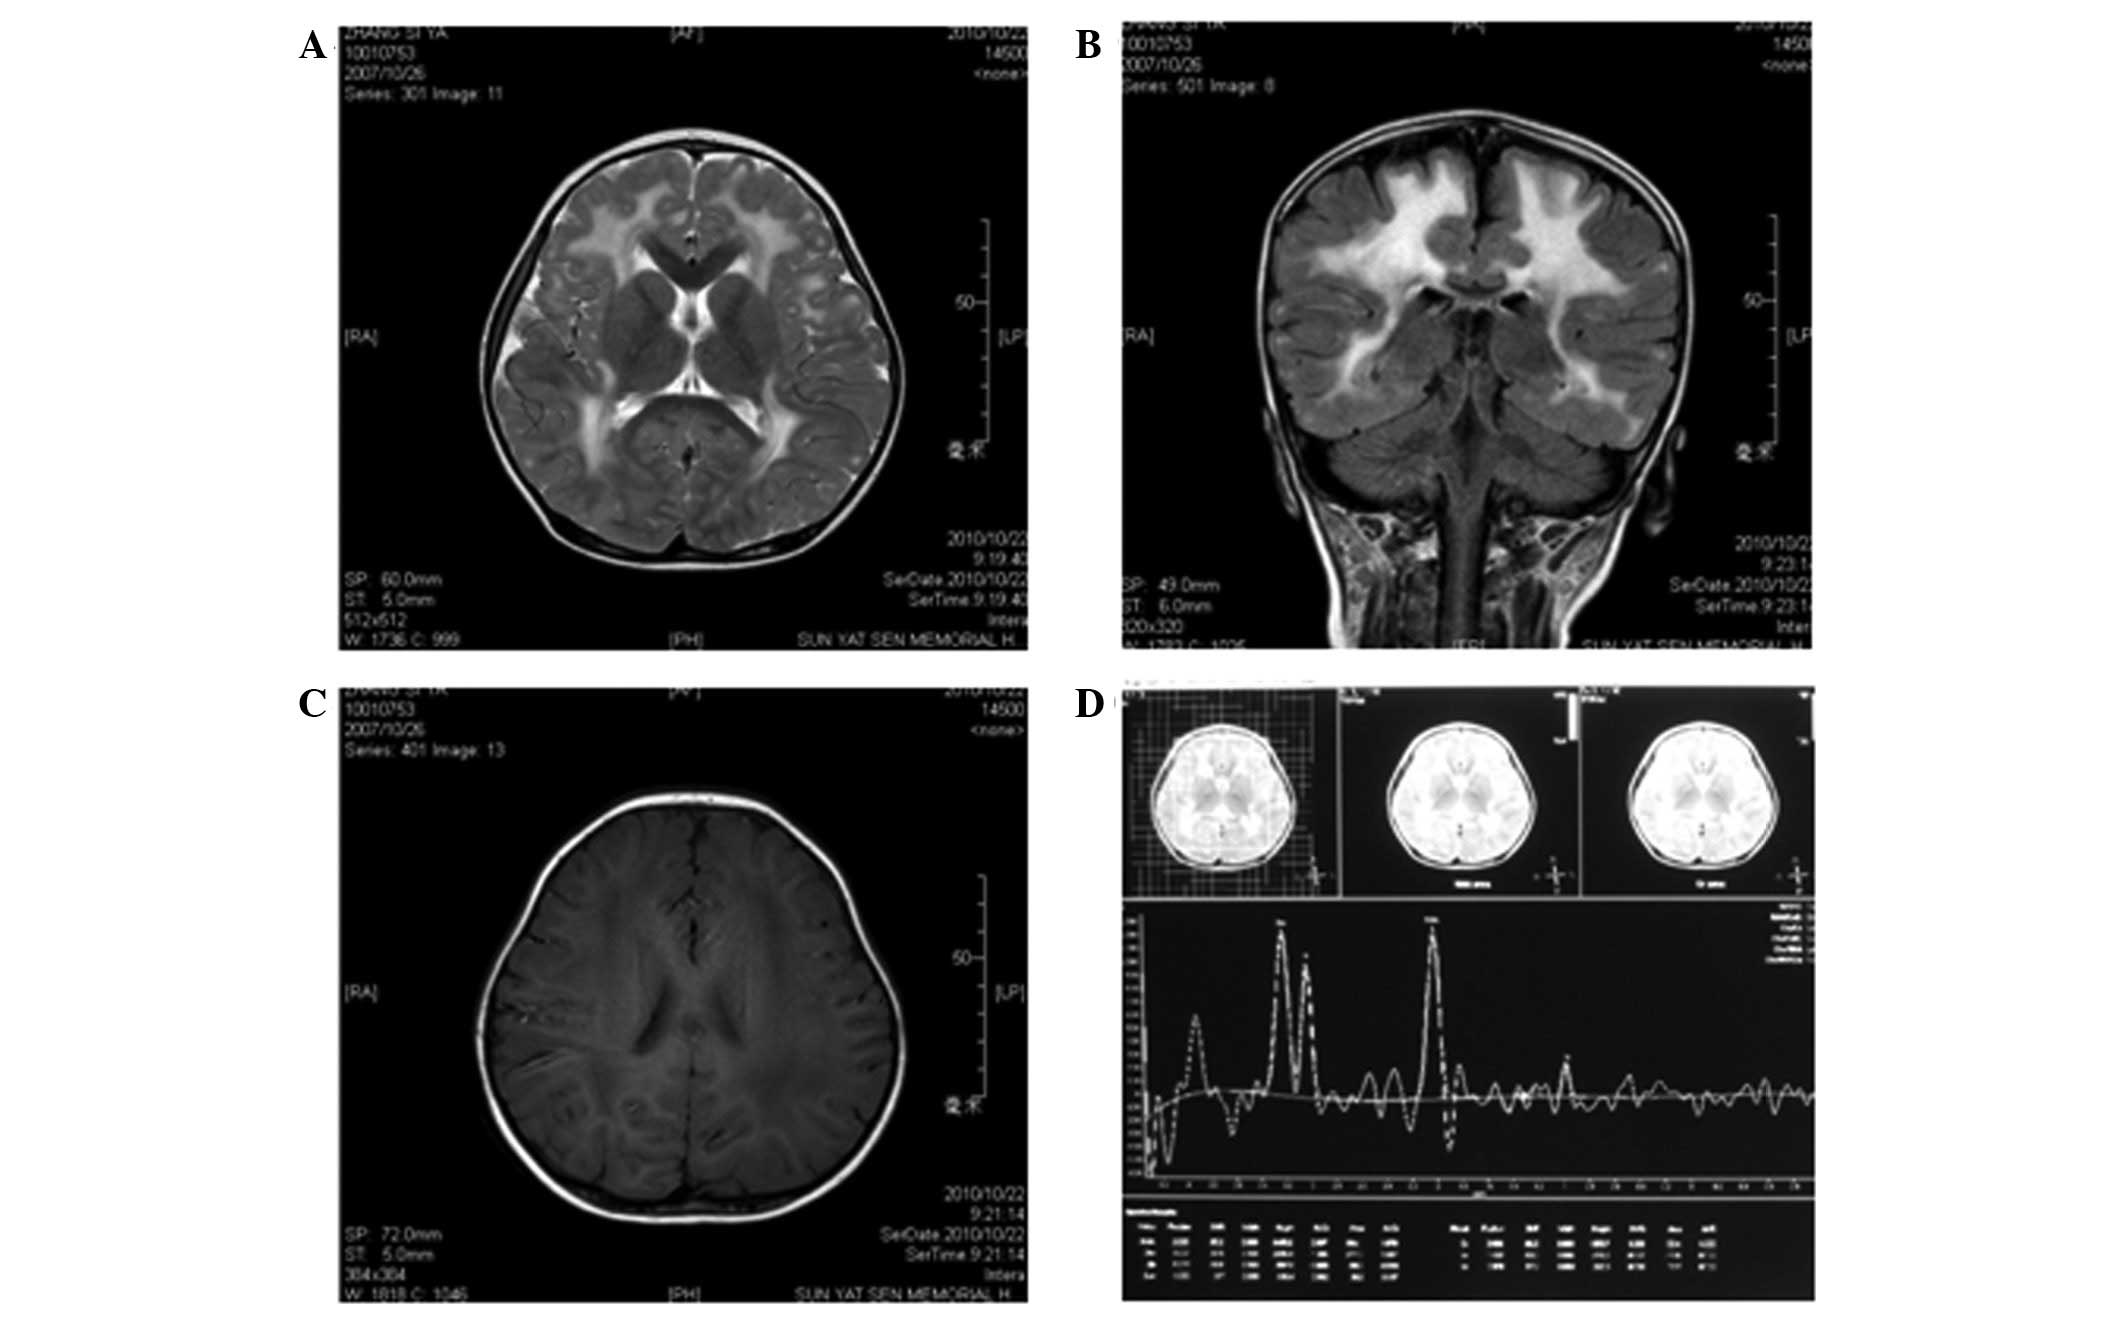

Neuroimaging

MRI was performed at Sun Yat-sen Memorial Hospital

of Sun Yat-sen University when the patient was 3 years old.

T1-weighted images revealed symmetrical, low signal intensity in

the white matter of the frontal, parietal, temporal and occipital

lobes; however, the cortex was normal (Fig. 1C). T2-weighted images revealed

lesions with abnormally high signal intensity in the white matter

of the frontal, parietal, temporal and occipital lobes (Fig. 1A and B). The ventricles,

cerebellum, basal ganglia and pons were normal. Semi-quantitative

magnetic resonance spectroscopy (MRS) revealed that the

N-acetylaspartate/creatine (NAA/Cr) and choline/creatine (Cho/Cr)

metabolite ratios were within normal ranges. However, the

myoinositol/creatine (mI/Cr) metabolite ratio was slightly

increased (Fig. 1D).

| Figure 1.Magnetic resonance imaging (MRI)

results at 3 years of age. (A) Axial T2-weighted image and (B)

coronal T2-weighted fluid attenuated inversion recovery (FLAIR)

image show diffuse, symmetrical high signal intensities in the

cerebral white matter. (C) Axial T2-weighted image shows diffuse

low signal intensity in the cerebral white matter. (D) MRS [TR/TE =

(2,000 m/sec)/(35 m/sec)] of the parietal white matter at 3 years

of age demonstrated that the NAA/Cr and Cho/Cr ratios were normal,

but the MI/Cr ratio was slightly increased. TR, time of repetition;

TE, time of echo; Cho, choline; Cr, creatine; MI, myo-inositol;

NAA, N-acetylaspartate, MRS, magnetic resonance spectroscopy. |